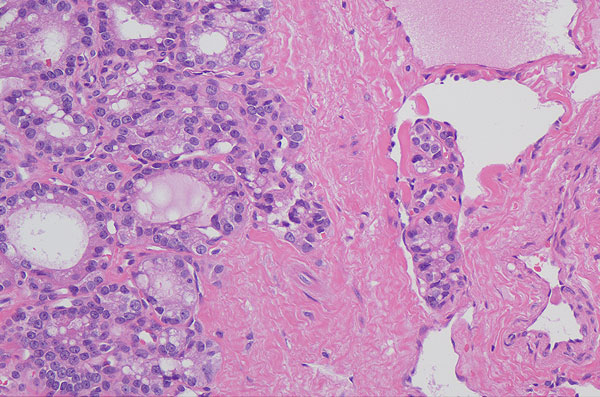

Hämatoxylin-Eosion Färbung:

Angioinvasion eines follikulären Schilddrüsenkarzinoms